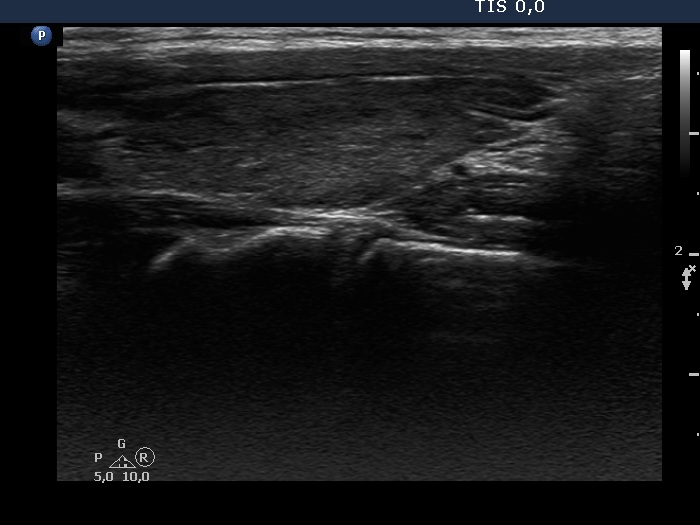

Consecutive patients with Hashimoto's thyroiditis - Case 3. (ultrasonographic picture 5)

Left lobe, longitudinal scan.